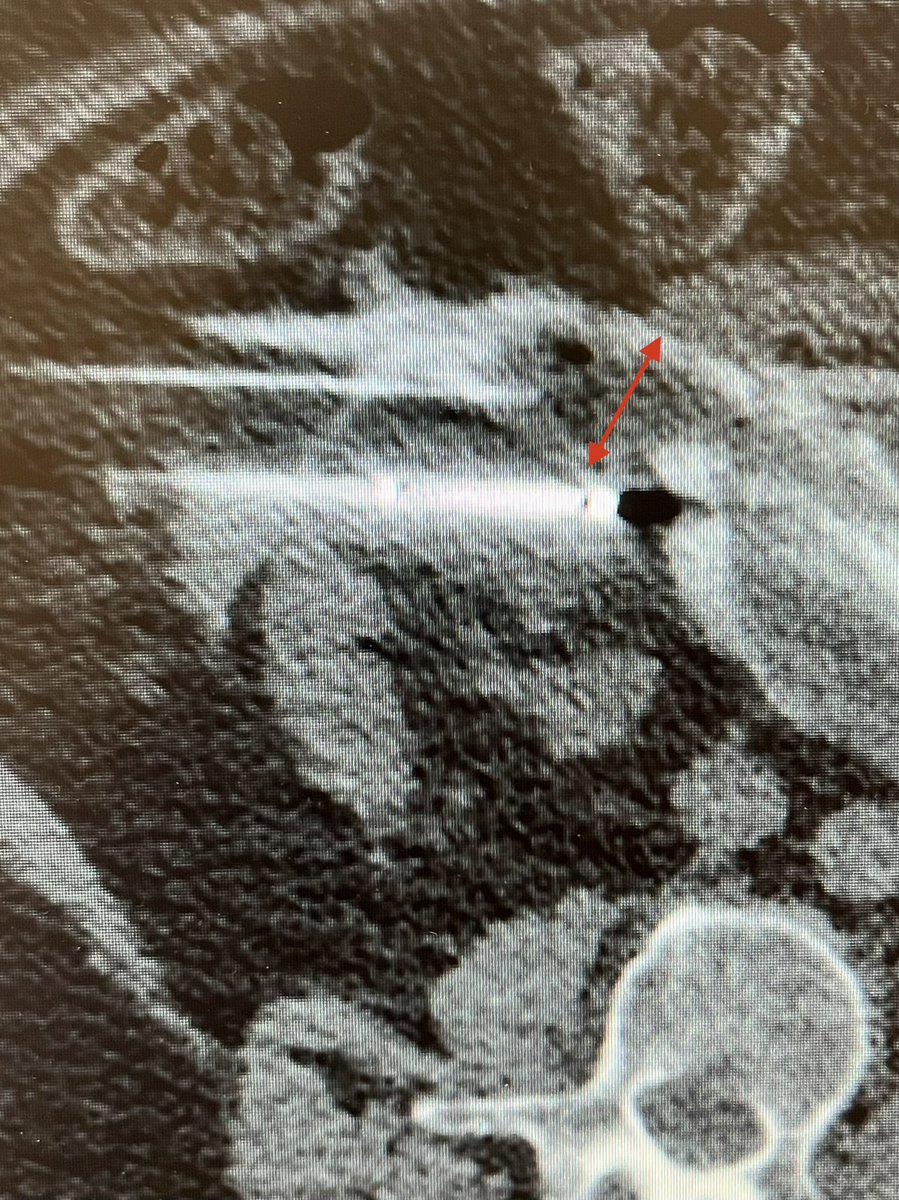

Anterior renal mass abutting small bowel. Ablation declined by outside IR due to location. Bowel displaced with hydrodissection for safe cryoablation. Thx for the tips in AJ Gunn’s SIR ECS recent webinar. The Dotter Institute Boston Scientific

Anterior renal mass abutting small bowel. Ablation declined by outside IR due to location. Bowel displaced with hydrodissection for safe cryoablation. Thx for the tips in <a href="/ajgunnmd/">AJ Gunn</a>’s <a href="/SIR_ECS/">SIR ECS</a> recent webinar. <a href="/dotter_IR/">The Dotter Institute</a> <a href="/bostonsci/">Boston Scientific</a>